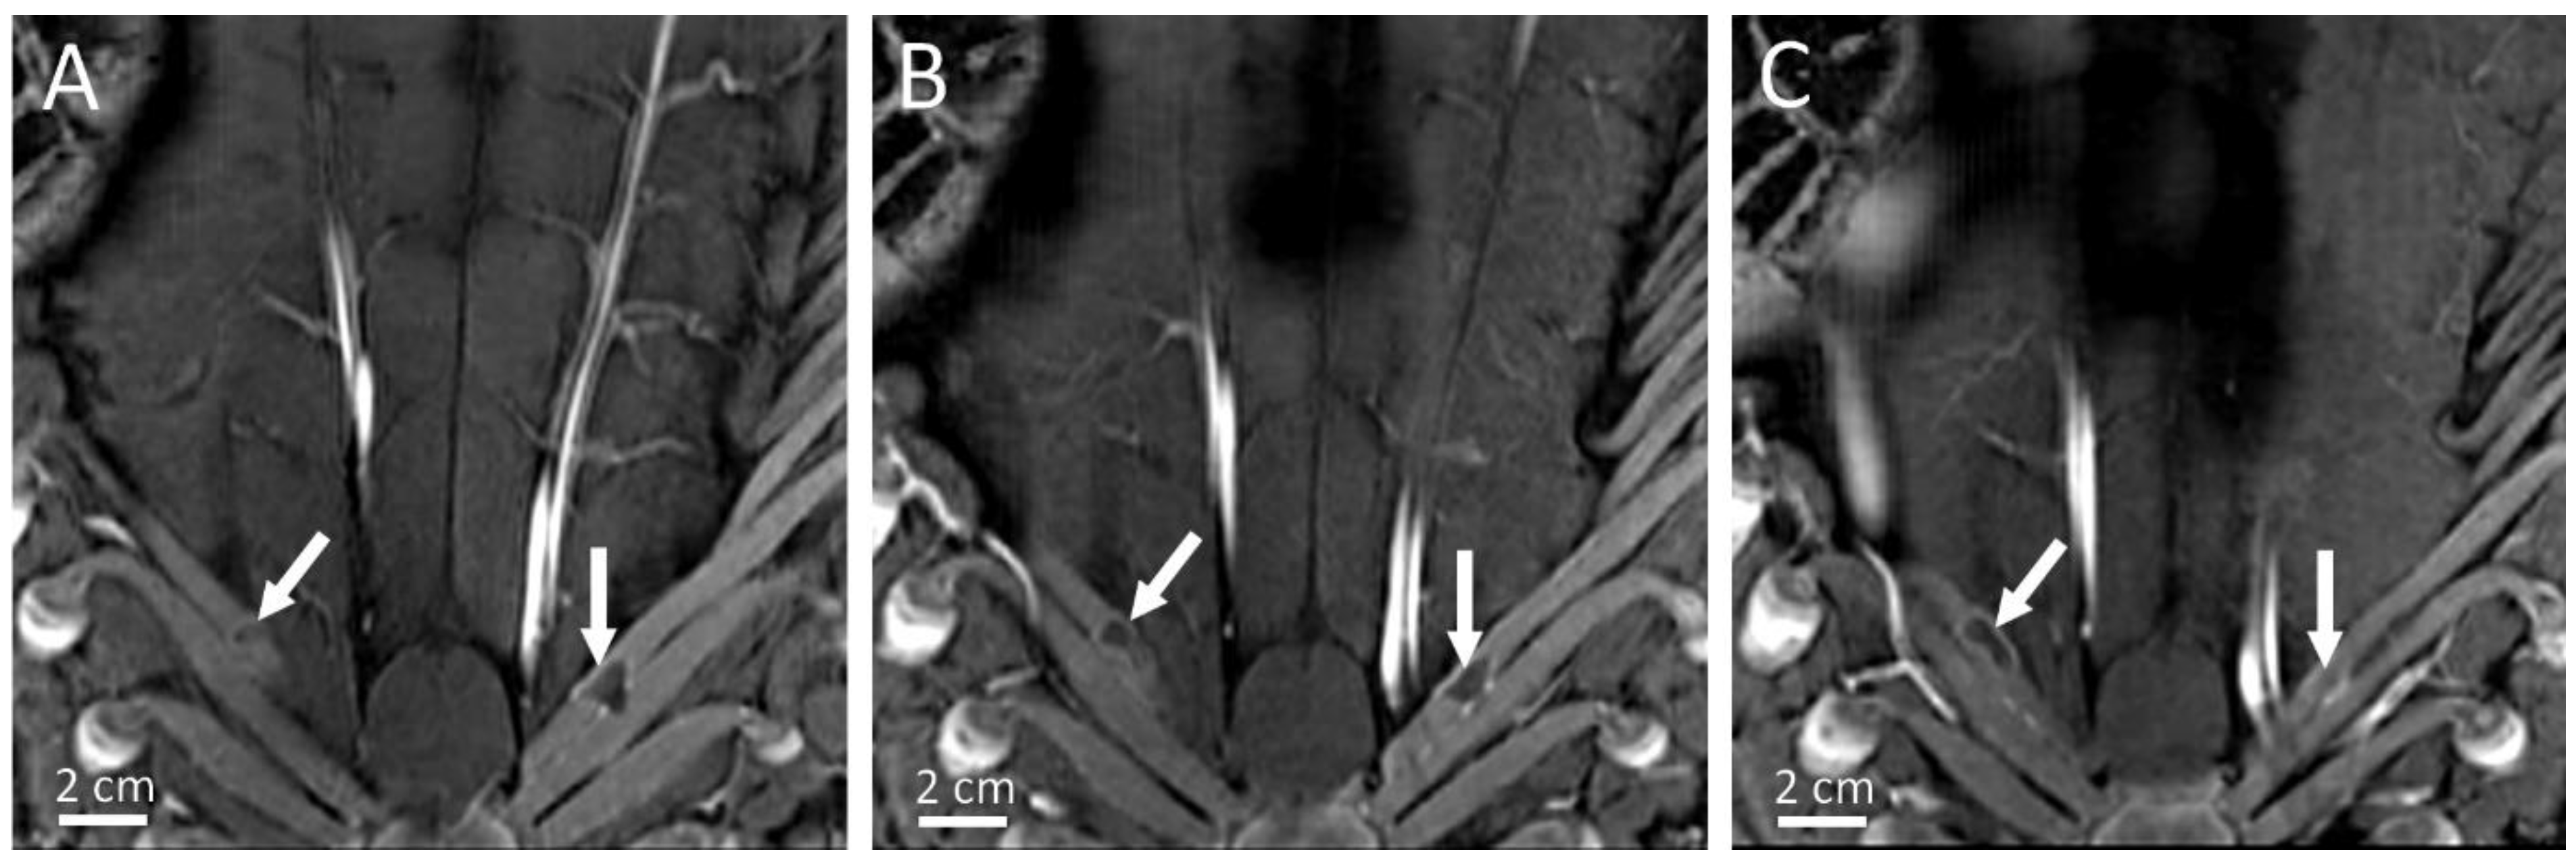

- Lorton, O.; Guillemin, P.C.; M′Rad, Y.; Peloso, A.; Boudabbous, S.; Charbonnier, C.; Holman, R.; Crowe, L.A.; Gui, L.; Poletti, P.A.; et al. A Novel Concept of a Phased-Array HIFU Transducer Optimized for MR-Guided Hepatic Ablation: Embodiment and First In-Vivo Studies. Front. Oncol. 2022, 12, 899440. [Google Scholar] [CrossRef] [PubMed]

| Pig | RF Ablation Size (mm3), from MR Images (along AP, LR and HF Axes) | Temperature Reached During HIFU Ablation (°C) | HIFU Ablation Longest Axis (mm) from MR Images; See Figure 6 and Figure 7 | HIFU Ablation Longest Axis (mm), from Gross Pathology; See Figure 6 and Figure 7 | Planned Center-to-Center Distance between the RF and MRgHIFU Ablations (mm), from MR Images | Center-to-Center Distance between the RF and MRgHIFU Ablations (mm), from Gross Pathology | Center-to-Center Distance between the RF and MRgHIFU Ablations (mm), from MR Images | Near-Field Side Effects Grade |

|---|---|---|---|---|---|---|---|---|

| 1 | 4.9 × 6.1 × 4.8 | 63 | - | - | 0 | - | - | 1a |

| 2 | 7.2 × 6.3 × 9.2 | 86 | 6.9 | - | 11.8 | - | 10.1 | 1a |

| 3 | 4.6 × 3.7 × 4.5 | 85 | 15.8 | 16.5 | 6.7 | 3.6 | 3.2 | 1a |

| 4 | 6.7 × 6.1 × 6.8 | 86 | 7.4 | 7.9 | 16.1 | 16.0 | 16.2 | 1a |

| 5 | 5.1 × 4.7 × 6.2 | 62 | 21.1 | 23.2 | 18.4 | 24.2 | 24.1 | 1a |

| 6 | 3.0 × 4.6 × 5.5 | 58 | 14.0 | 15.0 | 11.2 | 10.3 | 10.3 | 1b |